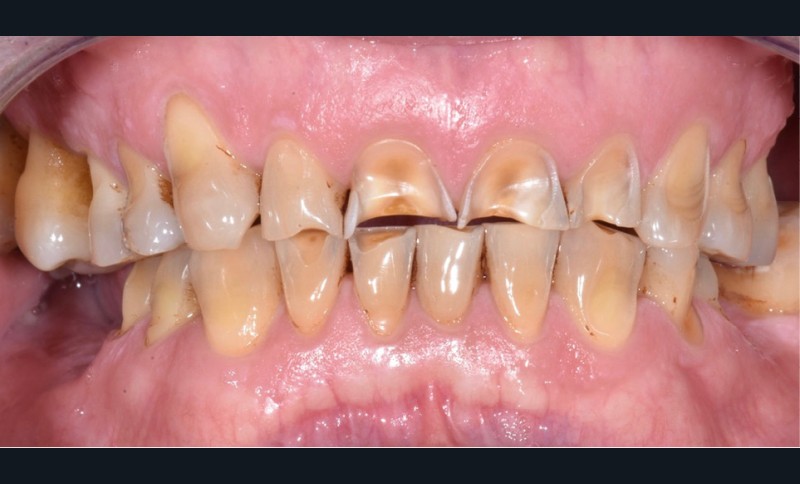

Le cas clinique présenté ici illustre cette démarche thérapeutique. À la suite d’un diagnostic de cancer des voies aérodigestives supérieures, un patient de 68 ans a bénéficié d’un traitement par radiothérapie cervico-faciale, terminée depuis plus de 2 ans. Il souhaite désormais retrouver une réhabilitation fonctionnelle et esthétique de sa cavité orale. Il indique que le délabrement de ses dents antérieures est à l’origine d’un important préjudice esthétique, qui l’a conduit à ne plus sourire. De plus, ses dents absentes réduisent fortement ses capacités masticatoires. Ces différents facteurs influent donc directement son estime de soi et sa qualité de vie, paramètres clés de la rémission dans le cadre oncologique. À l’examen clinique, il présente une perte de calage postérieur, avec des édentements terminaux secteur 2 et 4, ainsi que de volumineuses pertes de substance au niveau des dents présentes (fig. 1).